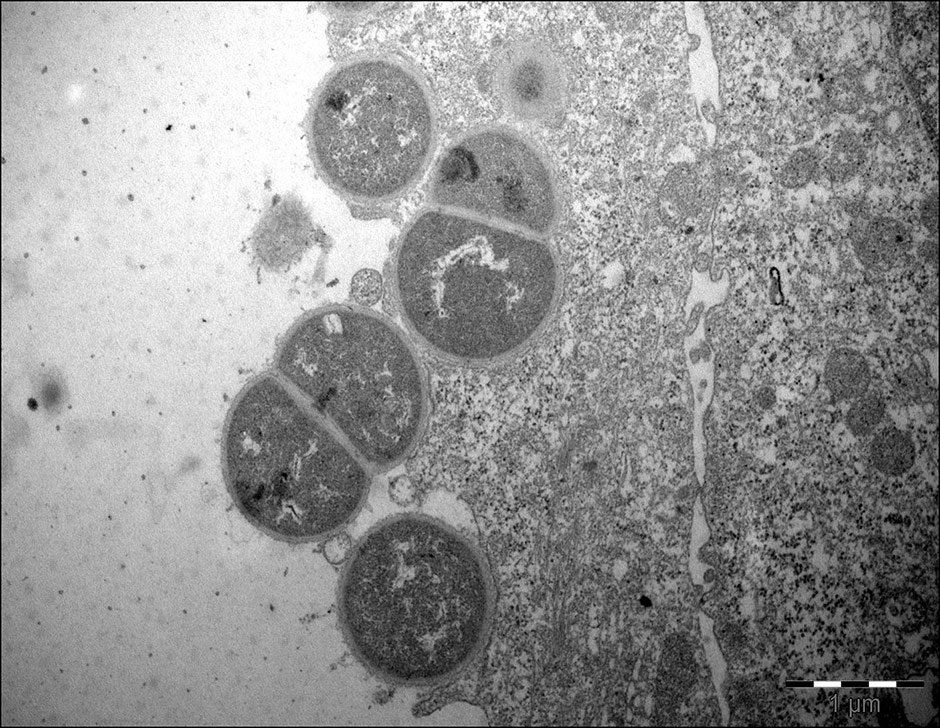

Figure 2

Transmission electron micrographs, demonstrating M. catarrhalis(strain 287) invasion in Detroit 526 pharyngeal cells.

Invasion of human respiratory epithelial cells has been observed mainly in vitro [68, 69]. Invasion is regulated by the expression of LOS, UspA1 [68] and probably other outer membrane components. Slevogt et al. first described the capacity of M. catarrhalis to invade respiratory tract epithelial cells in vitro [69], and Heiniger et al. demonstrated its capacity to invade sub-epithelial pharyngeal lymphoid tissue in vivo [70]. It seems that invasion allows M. catarrhalis to escape killing by the host immune-system and extracellular antibiotics. The relevance and mechanisms of M. catarrhalisinvasion are incompletely understood, and further studies are warranted (fig. 2).

Acknowledgments:We thank Marion Jetter, PhD, for providing the transmission electron micrographs.